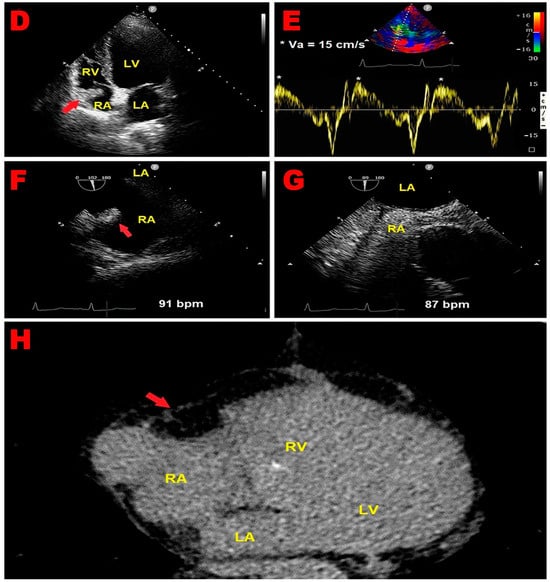

An 83-year-old male (BSA 1.75 m2, BMI 22.5 Kg/m2) affected by chronic renal failure (estimated glomerular filtration rate: 26 mL/min/m2), without previous cardiovascular history, was admitted to the emergency department of our institution due to the sudden onset of symmetric weakness with paresthesias involving both legs. Relevant upon physical examination was a blood pressure of 110/70 mmHg and a stage 2 sacral decubitus ulcer. The ECG showed sinus rhythm around 60 b.p.m with normal atrioventricular and intra-ventricular conduction; a single supraventricular extrasystole was recorded (Figure 2A). The patient was admitted to the internal medicine ward, where he received IV antibiotics (ceftriaxone 2 gr/die), fluid therapy (physiological solution 1500 mL/die), and anticoagulants (subcutaneous calcium–heparin 5000 I.U. every 12 h). An electromyography identified axonal sensorimotor polyneuropathy, and the patient was diagnosed with Guillain–Barré syndrome. Upon diagnosis, the patient was transferred to the Department of Neuromotor Rehabilitation, where he underwent treatment with acetyl-L-carnitine and motor rehabilitation. During hospitalization, the patient manifested a sudden onset of aphasia and confusional state. Contrast-enhanced CT scan of the brain excluded ischemic lesions, whereas brain magnetic resonance imaging (MRI) with contrast showed bilateral cortical and subcortical ischemic lesions involving the frontal and occipital lobes of both cerebral hemispheres (Figure 2B,C). The patient underwent serial ECGs and a 24 h ECG Holter monitoring; in the short-term monitoring, there was no evidence of AFib. Carotid ultrasonography revealed bilateral mild stenosis (25% degree) of the carotid bifurcation due to deposition of calcific atherosclerotic plaques. We performed a bedside TTE, which showed small chamber sizes, normal biventricular systolic function, first-degree diastolic dysfunction, absence of relevant valvulopathies, and normal hemodynamics. From the apical four-chamber view, a suspected RA mass was detected with similar echogenicity as the surrounding myocardium. The mass occupied the infero-lateral portion of right atrial cavity, as demonstrated in Figure 2D. By placing a 5 mm sample volume of PW-TDI at the level of the mobile portion of the RA mass, this structure showed a cyclic motion concordant with the surrounding myocardial tissue. The peak antegrade velocity of RA mass was 15 cm/s and remained stable at each cardiac cycle (Figure 2E). A subsequent TEE was performed for a more detailed evaluation of the suspected RA mass and to determine whether there were other potential cardiac sources of emboli. TEE documented the same echogenic structure projecting into the RA cavity, visualized in proximity of the atrioventricular junction in close proximity of the RA infero-lateral wall (Figure 2F). Contrast-enhanced TEE demonstrated the integrity of the interatrial septum, thus excluding a patent foramen ovale (Figure 2G). We also excluded the presence of thrombi within the left atrial appendage and atherosclerotic debris. Lastly, the patient underwent contrast-enhanced chest CT scan, showing a homogenously hypodense formation occupying the infero-lateral portion of RA cavity, compatible with adipose tissue of the right atrioventricular groove (Figure 2H). In light of the aforementioned findings, the suspected RA mass was more properly defined as RA pseudomass, ascribed to the systolic infolding of the lipomatous right atrioventricular junction, in close continuity with RA infero-lateral wall. The ischemic lesions detected on brain MRI were, therefore, attributed to the cerebral embolization of carotid atherosclerosis. After three months of hospitalization, the patient was discharged on oral anticoagulation (warfarin 5 mg according to the International Normalized Ratio) and statin therapy (rosuvastatin 5 mg/die).

Figure 2.

(A) Twelve-lead electrocardiogram, showing sinus rhythm with normal atrioventricular and intra-ventricular conduction, single supraventricular extrasystole. (B,C) Diffusion-weighted magnetic resonance imaging of the brain, revealing bilateral cortical and subcortical ischemic lesions (red arrows) involving frontal and occipital areas of both cerebral hemispheres. (D) Transthoracic echocardiography. Apical four-chamber view, showing a suspected RA mass (red arrow), with similar echogenicity as the myocardium, occupying the infero-lateral portion of the right atrial cavity. (E) PW-TDI performed to assess the mass motility. By placing a 5 mm sample volume at the level of the mobile portion of the suspected RA mass, this structure showed a cyclic motion that was concordant with surrounding myocardial tissue. The peak antegrade velocity of RA mass was 15 cm/s and remained stable at each cardiac cycle. (F) Transesophageal echocardiography. Mid-esophageal bicaval view, demonstrating an echogenic structure (red arrow) projecting into the RA cavity, visualized in proximity of the atrioventricular junction, in close proximity with RA infero-lateral wall. (G) Contrast-enhanced transesophageal echocardiography highlighting the integrity of the interatrial septum, thus excluding patent foramen ovale. (H) Contrast-enhanced chest CT scan showing a homogenously hypodense formation (red arrow) occupying the infero-lateral portion of RA cavity, compatible with the adipose tissue of the right atrioventricular groove. CT, computed tomography; LA, left atrium; LV, left ventricle; PW, pulsed wave; RA, right atrium; RV, right ventricle; TDI, tissue Doppler imaging; * Va, mass peak antegrade velocity.